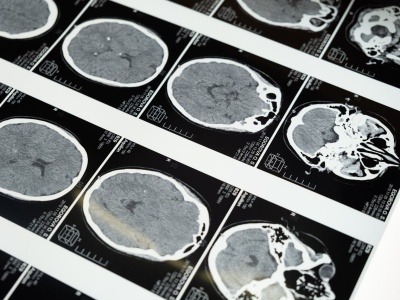

Nowe badanie pokazuje, że połączenie dwóch terapii epigenetycznych może skuteczniej hamować rozwój śmiertelnych guzów mózgu u dzieci. Artykuł Nowe badanie: podwójna terapia daje nadzieję na leczenie raka mózgu u dzieci pochodzi z serwisu Alert Medyczny.